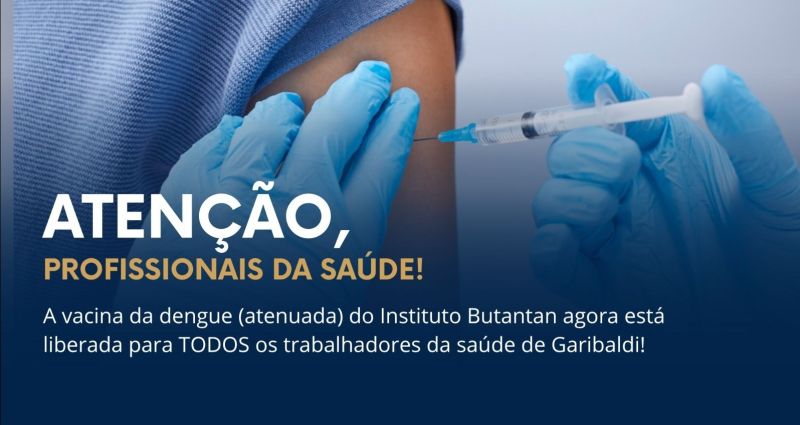

Medicamento será administrado por injeção intramuscular em recém-nascidos e lactentes nos períodos de maior circulação do vírus

Agência Nacional de Vigilância Sanitária (Anvisa) aprovou na segunda-feira (30) o registro do Enflonsia (clesrovimabe), da farmacêutica Merck Sharp & Dohme, como um medicamento para a prevenção do vírus sincicial respiratório (VSR).

O medicamento será oferecido como uma solução injetável, a ser administrada por via intramuscular em recém-nascidos e bebês lactentes nos períodos de maior circulação do VSR.

Geralmente, a doença é mais severa nos primeiros seis meses de vida, especialmente em bebês prematuros e em crianças com outras condições de saúde, como cardiopatias congênitas ou doença pulmonar crônica da prematuridade.

Nos pacientes que se submetem a cirurgia cardíaca com circulação extracorpórea, é recomendável administrar uma dose extra após a estabilização clínica, uma vez que a circulação extracorpórea pode diminuir os níveis do anticorpo no sangue.

Vírus sincicial respiratório (VSR)

O vírus causa infecções respiratórias, especialmente bronquiolite em crianças e bebês. O Ministério da Saúde (MS) informa que o VSR é o responsável por aproximadamente 80% dos casos de bronquiolite e até 60% das pneumonias em crianças com menos de dois anos.

Calcula-se que uma em cada cinco crianças infectadas precise de atendimento ambulatorial e uma em cada 50 necessite de internação no primeiro ano de vida. De 2018 a 2024, contabilizaram-se 83.740 internações de recém-nascidos prematuros (menos de 37 semanas) em decorrência de complicações do vírus, como bronquite, bronquiolite e pneumonia.

No mês de dezembro do ano anterior, o MS começou a campanha nacional de vacinação contra o VSR.

A vacina, que o Sistema Único de Saúde (SUS) disponibiliza, é recomendada a gestantes a partir da 28ª semana com o intuito de prevenir bronquiolite em recém-nascidos.